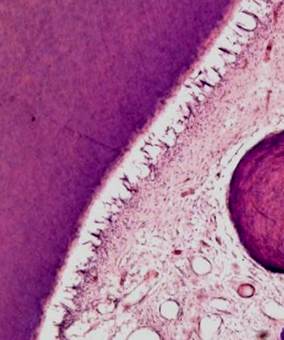

Рис. 1-4, а, б. Микропрепараты «Хронический остеомиелит челюстных костей, стадия секвестрации». а – костный секвестр (бесклеточный фрагмент костной балки - 1) и секвестральная соединительнотканная капсула (2), б – гнойное воспаление (гнойный экссудат состоит преимущественно из живых и погибших нейтрофильных лейкоцитов — гнойных телец) (3). Окраска гематоксилином и эозином, х200 (препараты Г.Н.Берченко) .